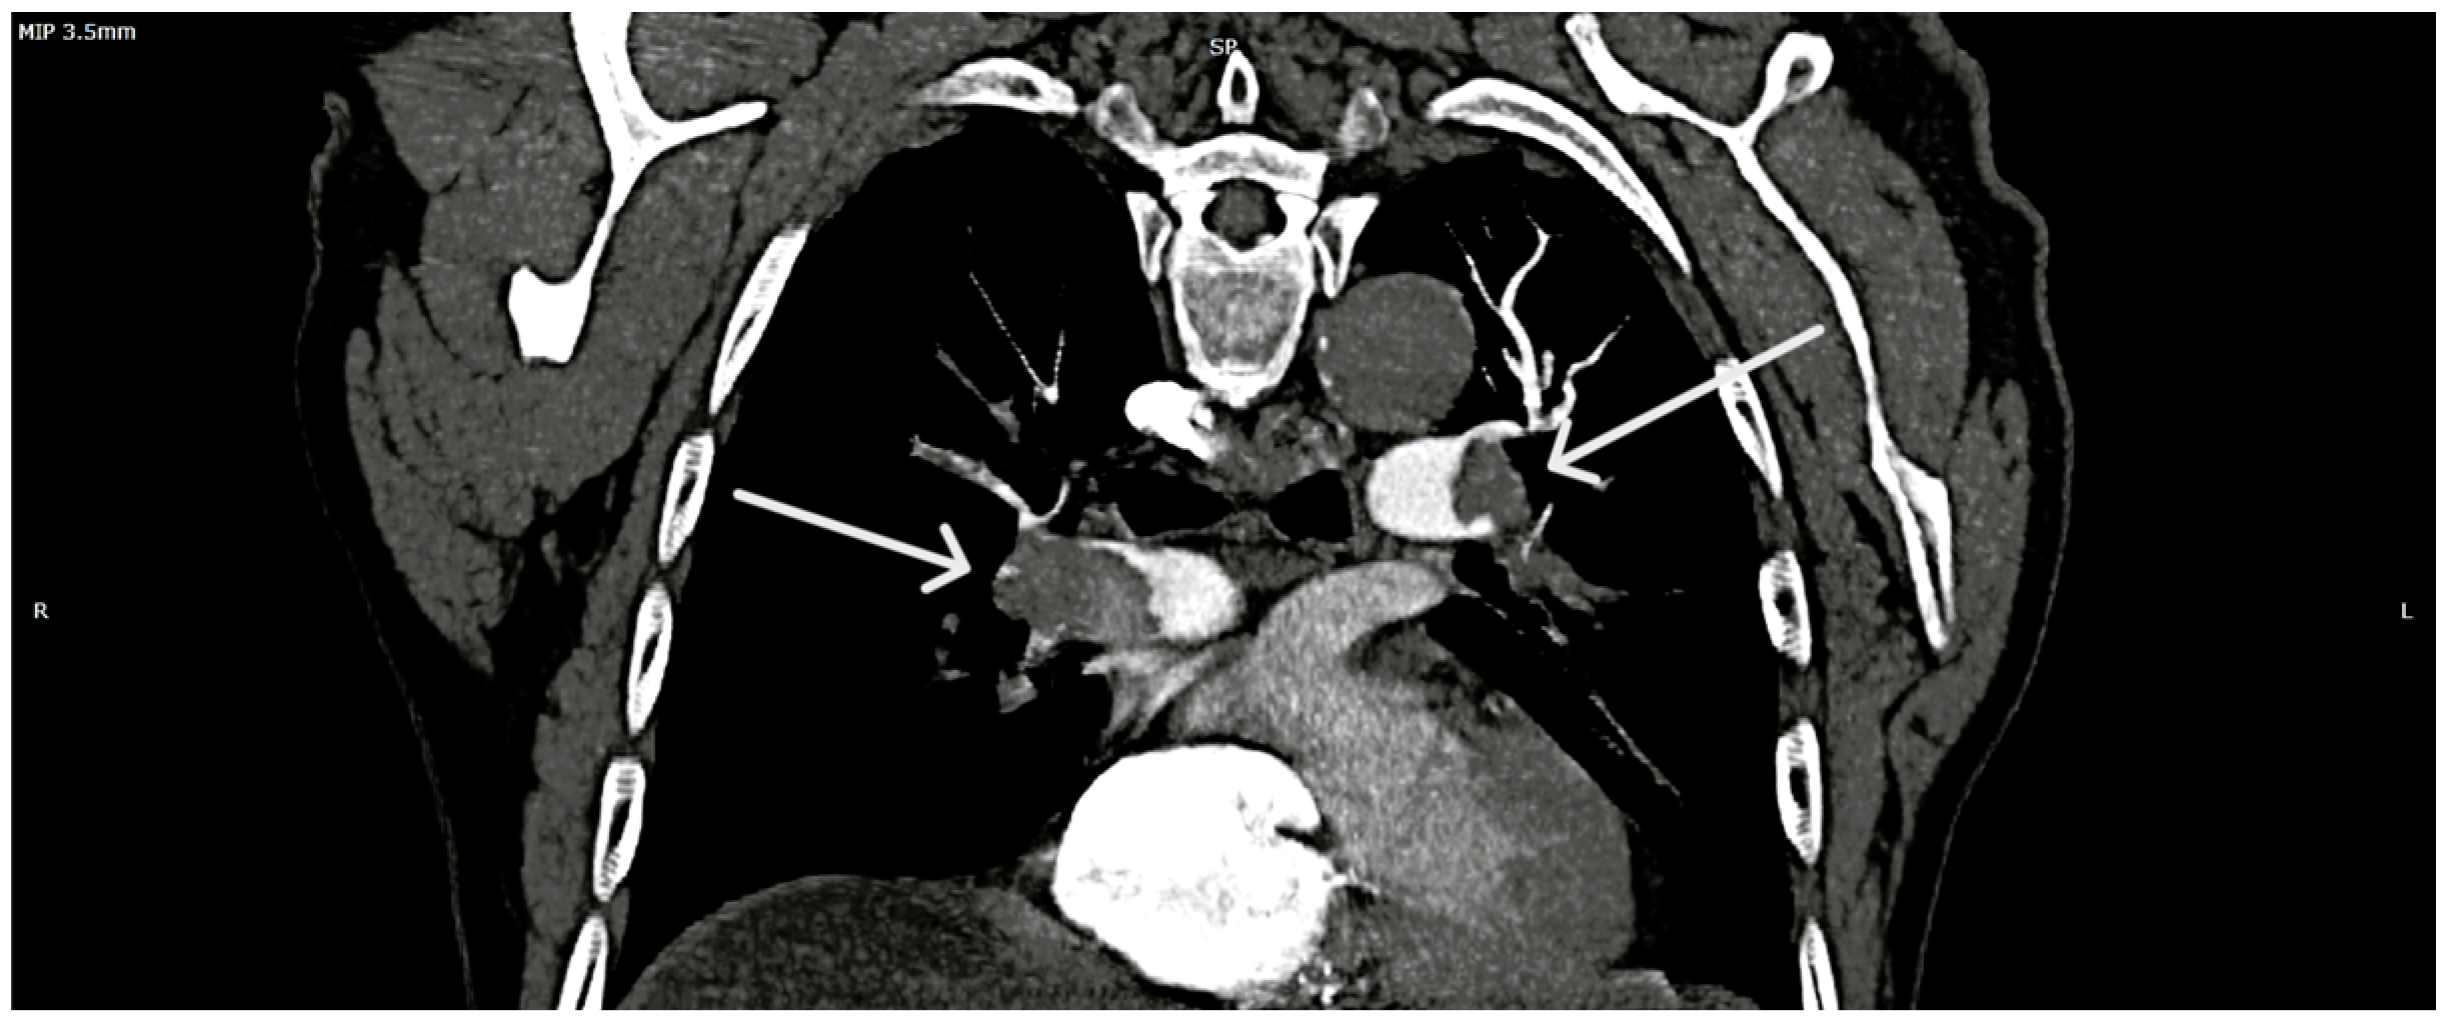

| POCUS-TTE—Parameters, Values and Risk Classification | |||

| RV/LV ratio | 1.39 | high | Intermediate-high-risk |

| TAPSE (mm) | 12 | low | Intermediate-high-risk |

| Parameter | Measurement | Interpretation |

|---|---|---|

| RV diameter | 46 mm (below tricuspid/pulmonary annulus) | Marked RV dilation |

| LV diameter | 33 mm | Normal size |

| RV/LV ratio | >1 | Consistent with acute RV pressure overload |

| RA size | Dilated | Elevated right-sided pressures |

| Pulmonary trunk diameter | 31 mm | Mild dilation; acute pulmonary hypertension |

| Tricuspid regurgitation, Vmax | 3.2 m/s | Increased RV pressure |

| RV—RA gradient | 40 mmHg | Significant RV overload |

| TAPSE | 12 mm | Markedly reduced RV systolic function |

| IVC | 19 mm, <50% collapse | Elevated RA pressure |

| Interventricular septum | Paradoxical motion | “D-shaped” LV; RV overload |

| Mobile RA thrombus | Large, serpentine, prolapsing through tricuspid | High embolic risk |

| Proximal DVT end | Lower third of superficial femoral vein | Non-adherent, unstable |

| Thrombus mobility | Free-floating, unstable | High embolization potential |

| Popliteal vein thrombosis | Nearly occlusive thrombus | Consistent with acute DVT |

| DVT extension | Distal into medial posterior tibial vein | Reflects propagation of DVT |